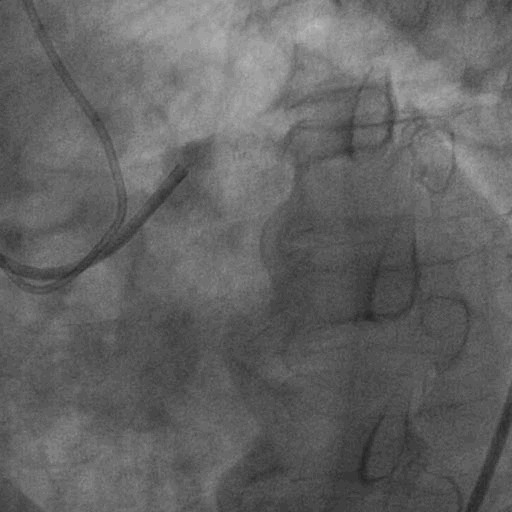

左冠造影:

右冠造影:

双侧造影: